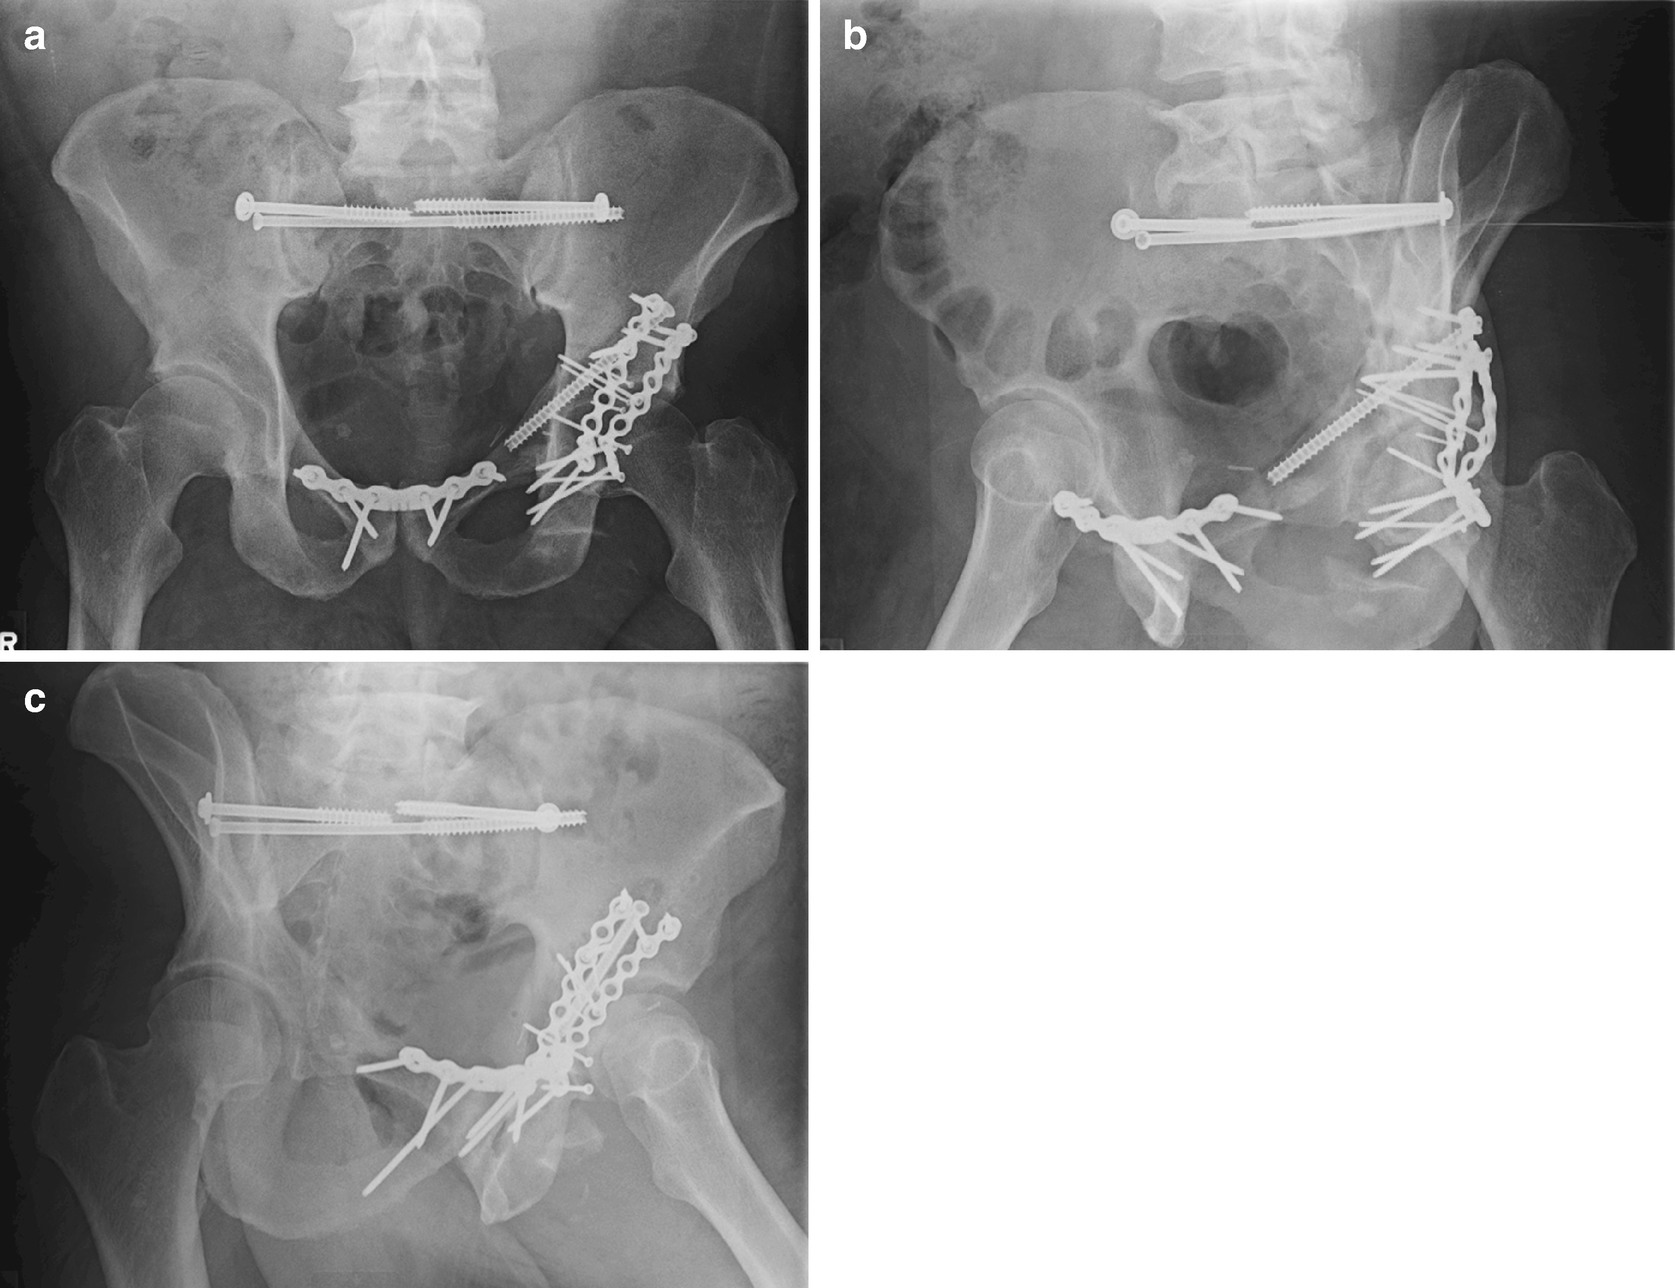

Acetabulum Two Column Fractures Springerlink

link.springer.com

Optimizing The Anatomic Reduction Of Complex Acetabular Fractures A Technical Enhancement To The Modified Stoppa Approach

clinmedjournals.org